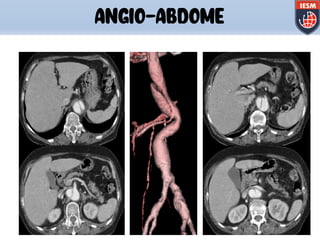

ANGIO-ABDOME

AVAq Com este programa é possível fazer

análise e medidas de volume, distância e

angulação dos vasos inclusive em em 3D .

q Visualizar o tamanho de estenoses.

q Fazer comparação quantitativa exata em

estudo sequencial para avaliar a

progressão da doença.

AVA

(Advanced Vessel Analysis)

Aneurisma de Aorta Abdominal